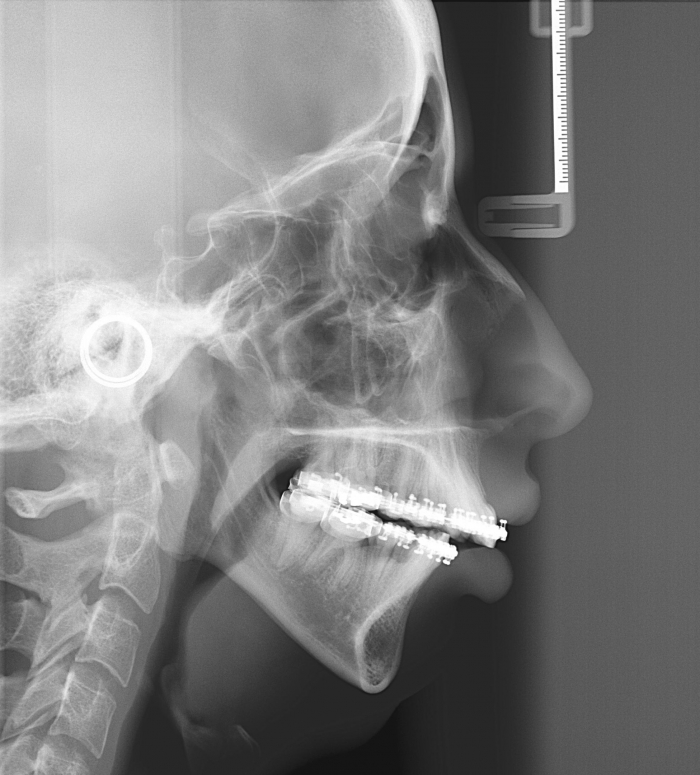

Telerradiografia inicial

Telerradiografia após a cirurgia